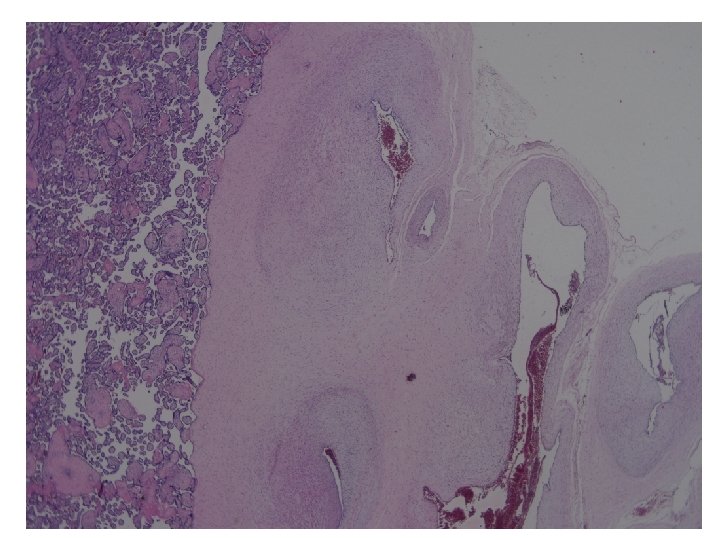

Subamniotic hematoma-20 X

Pathology No. 1594480 l Diagnosis ¡Placenta l. Retroplacental hematoma, compatible with abruptio placenta ¡Umbilical cord l. Velamentous umbilical cord insertion, with subamniotic hematoma